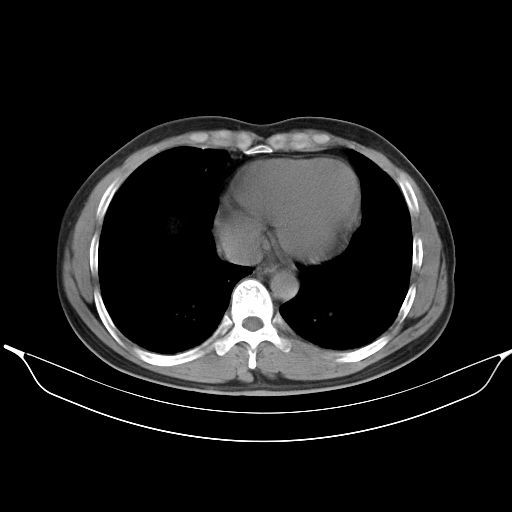

标题: CT25490:男,40岁,体检发现;无其它不适。 [打印本页]

标题: CT25490:男,40岁,体检发现;无其它不适。

考虑右下肺周围性肺癌并肺内多发转移,纵隔淋巴结转移!

支持 !考虑右下肺周围性肺癌并肺内多发转移,纵隔淋巴结转移,(气管前腔静脉后,隆突下,主动脉弓下都有了)

以下是引用wufeisheng在2010-4-1 23:09:00的发言:[br]考虑右下肺周围性肺癌并肺内多发转移,纵隔淋巴结转移!